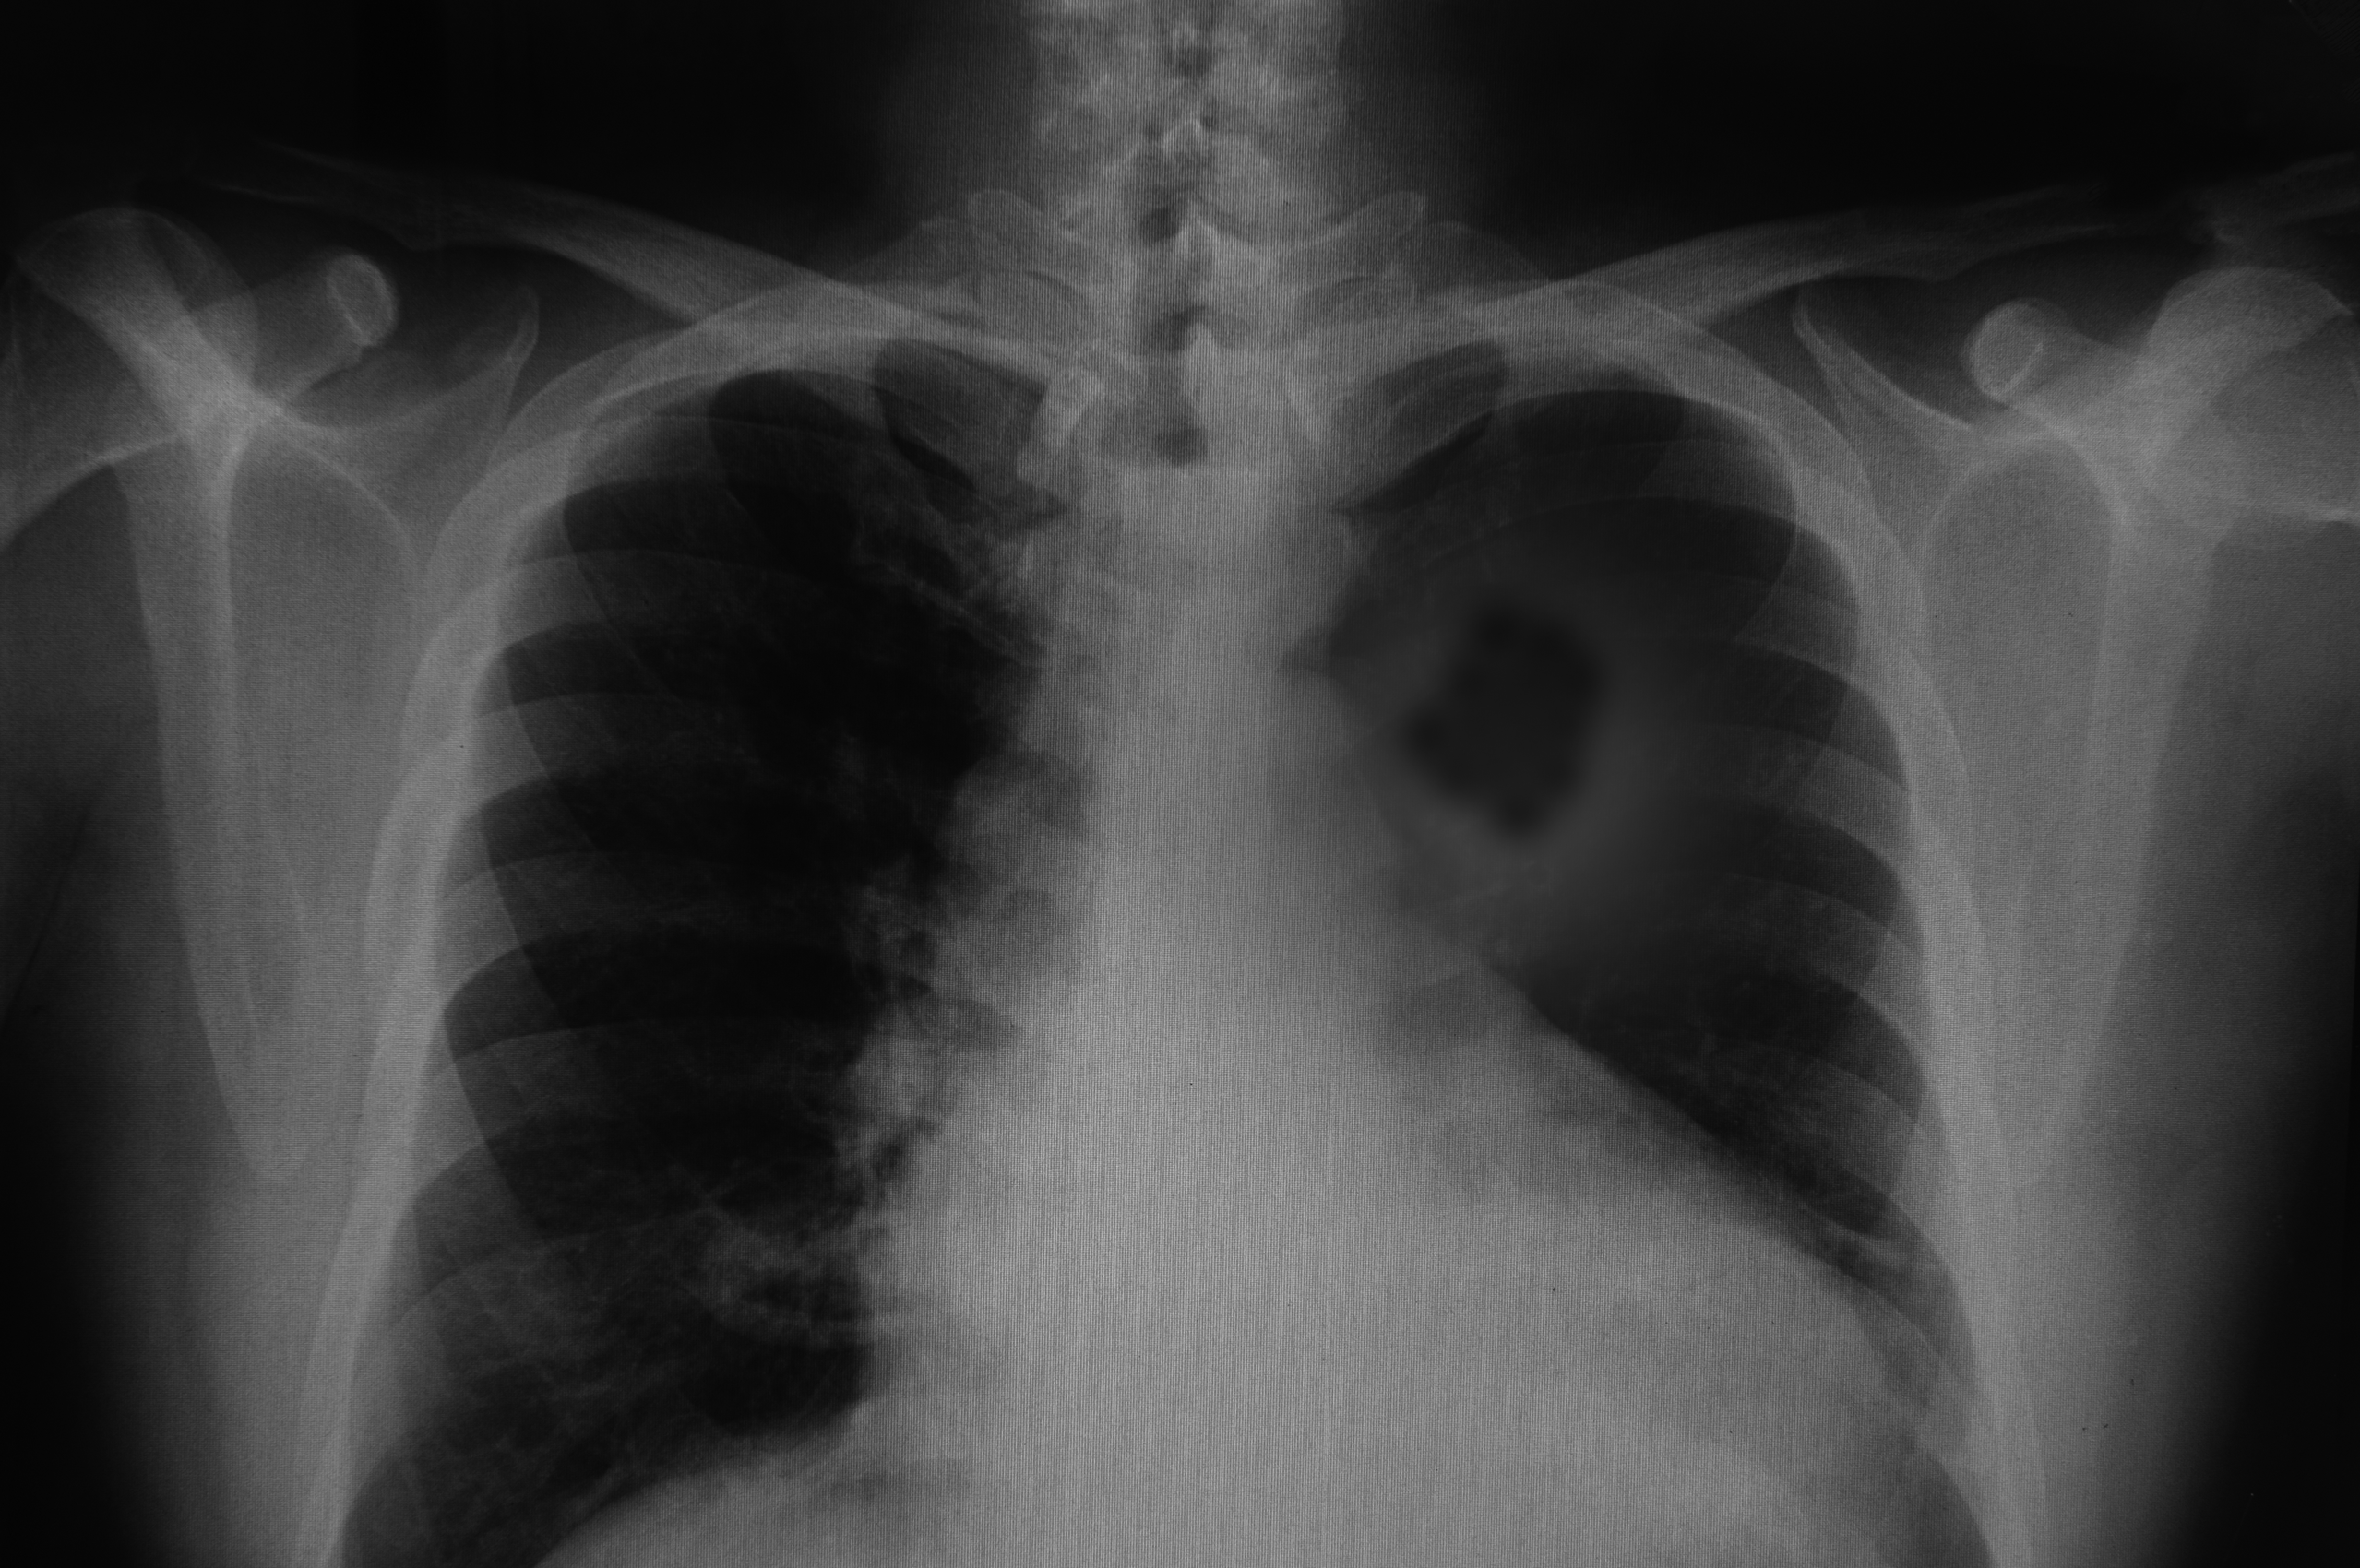

Get Lung Cancer Rib Pain UK. Lung cancer related back pain may be generalized like a muscle ache or sharp like a pinched nerve. Pain has an enormous effect on your quality of life, so if you are experiencing pain related to your lung cancer, alert your medical team.thinkstock.

This growth can spread beyond the lung by the process of metastasis into nearby tissue or other parts of the body. Rib pain can be especially felt on coughing as the underlying and surrounding structures are associated with the coughing system and may move while coughing. However, relatively more lung cancers are being diagnosed in people who have never smoked.

The formation of cancerous cells that originates from lungs is called lung cancer. Other symptoms include fractures, constipation or decreased alertness due to high. Stay positive and have strong mental health to face challenges and pain during treatment and recovery. Rib cage pain can occur anywhere below your ribs, in your upper or lower chest, or above your belly button.